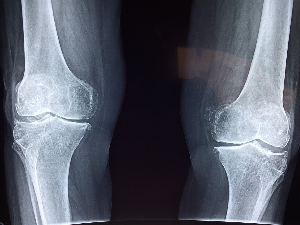

관절 건강을 위해 반드시 피해야 할 음식

1. 고칼로리 음식

관절 건강은 다양한 영향을 받으나 특히, 비만으로 인한 체중 증가는 관절에 큰 무리를 주어 관절 손상의 지름길입니다.

2. 당류, 트랜스 지방산

탄산음료, 과자, 사탕 등 과도한 당 섭취와 가공 식품, 패스트푸드 등 트랜스 지방산 섭취는 염증을 촉진하여 관절 건강에 무리를 줍니다.

결론적으로 인스턴트 등 가공 식품은 자제하고 자연식 위주의 균형 있는 식단을 유지는 것이 관절 건강에 유리합니다.